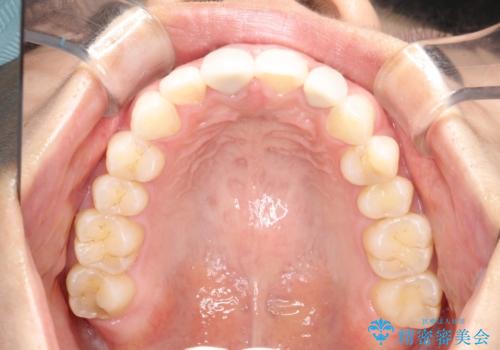

後戻りした歯並びをきれいにしたい

- ワイヤーで矯正した後戻りをマウスピースで治そうとしたが、使えなかったため再度ワイヤー矯正希望で来院されました。

装置はハーフリンガルを選択しています。

矯正としてはマウスピースでできましたが、患者さんの希望でワイヤー(ハーフリンガル)で矯正を行いました。

右下1が歯肉退縮していたため、アーチを拡げないように歯と歯の間を削って隙間をあけて並べています。